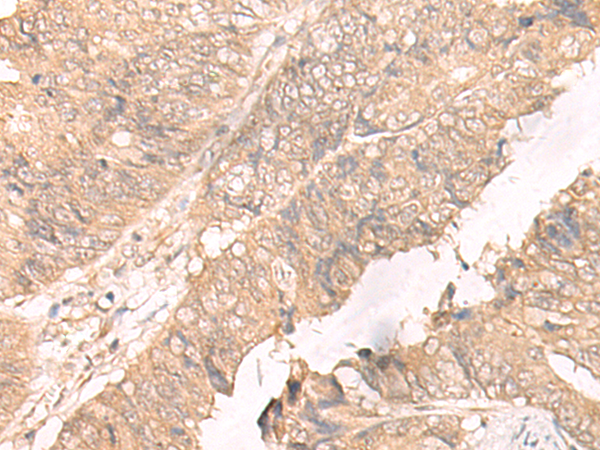

IHC positive control: |

Human colorectal cancer |

IHC Recommend dilution: |

40-200 |